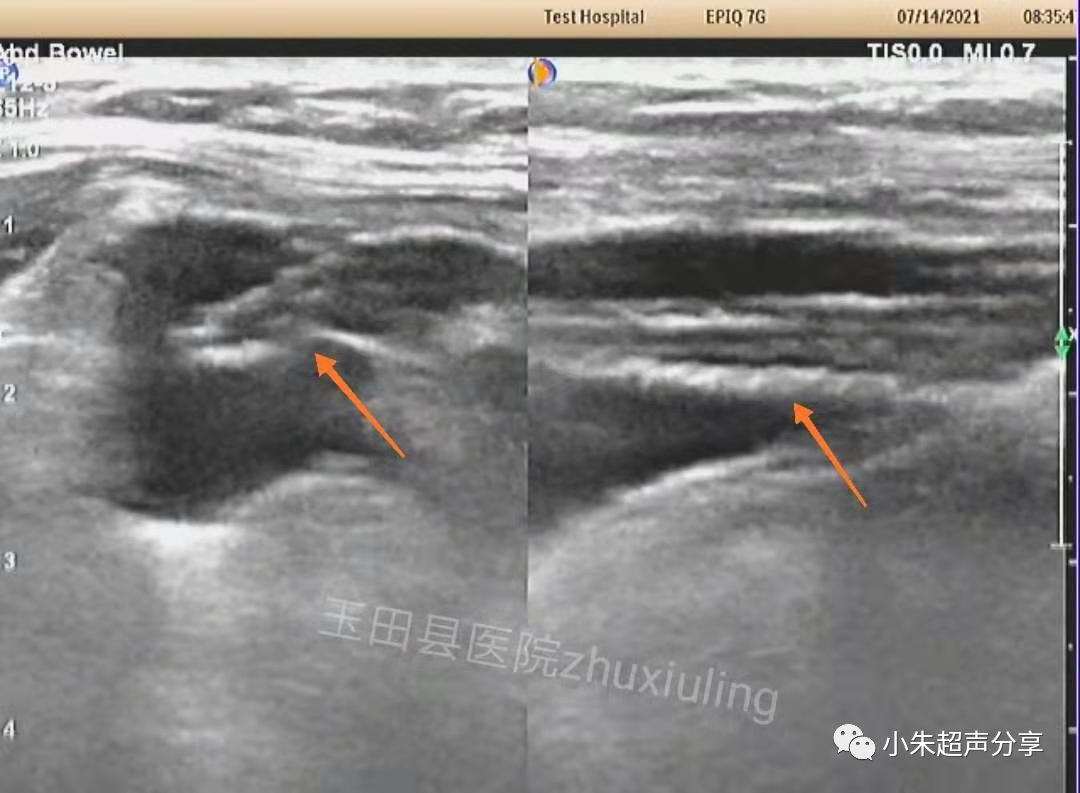

Case1:男,77岁,右侧腹股沟疝术后3天,右侧腹股沟区肿胀、疼痛。

超声检查:

与临床医生沟通后,临床医生行超声引导下腹股沟区抽液。站立位,抽出淡红色液体约50ml。

抽液后,右下腹液体减少、消失。补片紧贴前腹壁。

超声检查时,置入的补片一般表现为条索样强回声,部分可伴弱声影,周围有积液时显示清晰,无积液衬托时常常显示欠清或难以显示。因补片类型及置入时间的不同,补片的形态亦会有所不同。

使用补片修补腹股沟疝的常见并发症有补片周围发生积液或血清肿,两者均可继发感染修补失败或补片移位致疝复发;异物相关的并发症等。超声观察补片的内容一般包括:补片的位置、形态、大小及补片周围情况,注意补片有无移位、形态有无卷曲、补片周围有无积液及腹腔内容物回声等。

血清肿常表现为边界不清、形态不规则、透声差的无回声区,持续时间长者积液内可见多发分隔,无血流信号。在其内部或周边常可见到补片结构,病程长者,补片可卷曲变形呈波浪状(如Case2)。发现时应及时与手术医生沟通,必要时需多次穿刺抽吸,并需定期复查。Case1患者经抽液2次后好转出院(第1次抽出50ml淡红色液体,隔日抽出45ml淡黄色液体)。Case2患者经门诊保守治疗后痊愈。